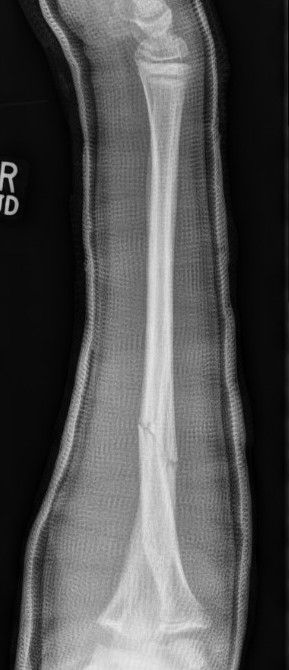

Types

Complete

Greenstick

Buckle / torus

Single or both bone